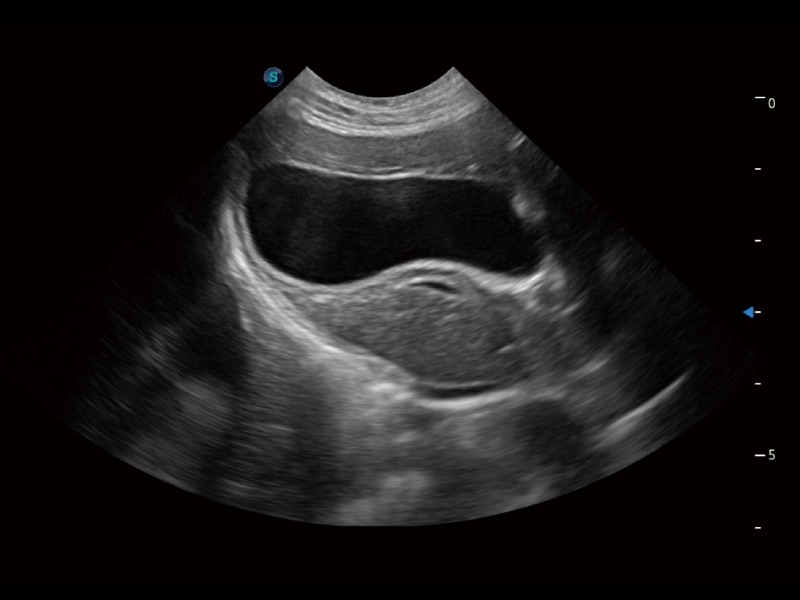

猫、中小型犬及小型异宠动物

ProPet 70 进一步提升了微米成像算法,更加注重对基础原始图像的还原和保留,在有效减少斑点噪声、增强组织边界显示的同时,避免过度优化丟失真实的解剖信息。

一键自动识别膀胱壁及自动测量膀胱容积,不受膀胱形状和大小的限制,帮助医生快速精准获得测量的数据。